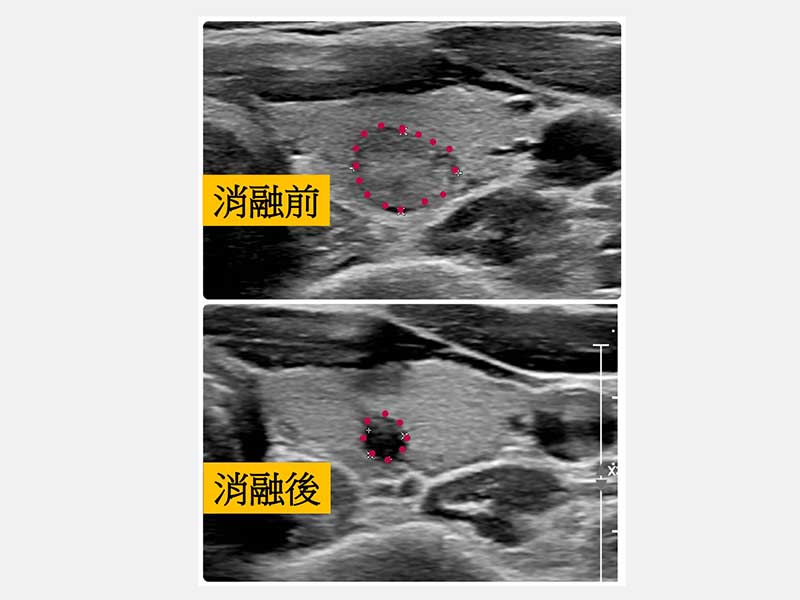

王呈綱醫師表示,當甲狀腺結節持續變大時,可能會造成脖子外觀突起、吞嚥問題或是腫痛症狀。微創射頻消融治療採用局部麻醉,可避免全身麻醉風險,並可於術中隨時監測患者聲音變化。微創射頻消融治療將細針進入甲狀腺結節,利用高頻電流在結節內部產生熱能,使結節組織壞死並逐漸縮小,追蹤一年的結節體積縮小比率可達80%-90%以上(因每人代謝吸收比率而有不同)。